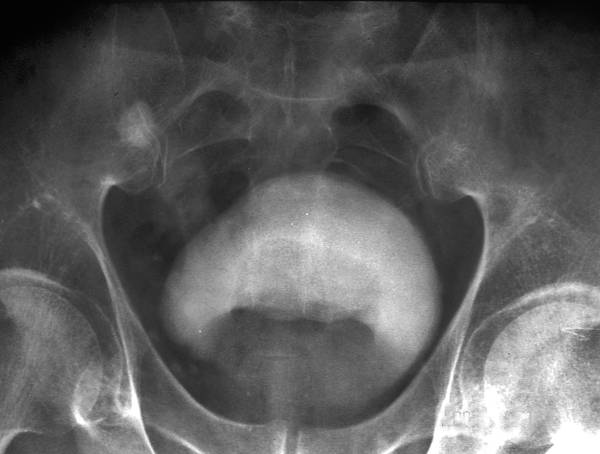

ЦИСТОГРАФИЯ

Цистография — метод исследования мочевого пузыря с помощью предварительного наполнения его жидким или газообразным контрастным веществом. Впервые её применил в 1902 г. Wittek. Цистография может быть нисходящей (экскреторной), восходящей (ретроградной) и антеградной. Нисходящую цистографию выполняют одновременно с экскреторной урографией, обычно спустя 1/2–1 ч после введения контрастного вещества.

К этому времени в мочевом пузыре накапливается достаточное количество контрастного вещества с мочой, что позволяет получить на снимке его чёткую тень (рис.).

Нисходящая цистограмма.

Нисходящую цистографию применяют в тех случаях, когда по каким-либо причинам невозможно ввести катетер в мочевой пузырь и, следовательно, выполнить восходящую (ретроградную) цистографию.

Противопоказания к ретроградной цистографии: острые воспалительные процессы в мочеиспускательном канале, мочевом пузыре, простате, семенных пузырьках и органах мошонки.

При цистографии мочевой пузырь должен быть наполнен контрастным веществом в достаточной степени, в противном случае тень пузыря на цистограмме окажется деформированной, что может повлечь за собой диагностическую ошибку. Нормальный, хорошо наполненный мочевой пузырь на цистограмме имеет гладкие ровные контуры. Его форма пузыря может быть круглой, овальной, продолговатой или пирамидальной. У мужчин чаще всего тень мочевого пузыря округлая, у женщин — овальная, причём поперечный диаметр больше продольного и присутствует некоторая вогнутость верхнего контура. Нижний край тени мочевого пузыря расположен на уровне верхней границы симфиза или выше её на 1,0–1,5 см, а верхний — достигает уровня III–IV крестцового позвонка. Верхний контур мочевого пузыря имеет несколько большие размеры, чем нижний. В норме на цистограмме мочеиспускательный канал и мочеточники не заполнены контрастным веществом.

Восходящая (ретроградная) цистография, выполняемая с жидким контрастным веществом, позволяет диагностировать ряд заболеваний: рентгенонегативные камни, инородные тела, аномалии развития, опухоли, туберкулёз мочевого пузыря, уретероцеле и дивертикулы.

Кроме того, можно определить размеры мочевого пузыря и количество камней в нём, установить степень вовлечения его стенки в паховую или бедренную грыжу, определить степень цистоцеле (опущение мочевого пузыря), а также изменения контуров мочевого пузыря при заболеваниях матки, её придатков, при наличии патологических процессов в паравезикальной клетчатке. При помощи цистографии можно диагностировать пузырные свищи, пузырно-мочеточниковый рефлюкс, провести дифференциальную диагностику между камнями мочевого пузыря, камнями мочеточника и очагами обызвествления в органах малого таза. Цистография позволяет обнаружить дефект наполнения по нижнему контуру пузыря в виде холма, характерный для аденомы простаты (рис.).

Ретроградная цистограмма: по нижнему контуру мочевого пузыря определяется дефект наполнения в виде холма, обусловленный аденомой простаты.